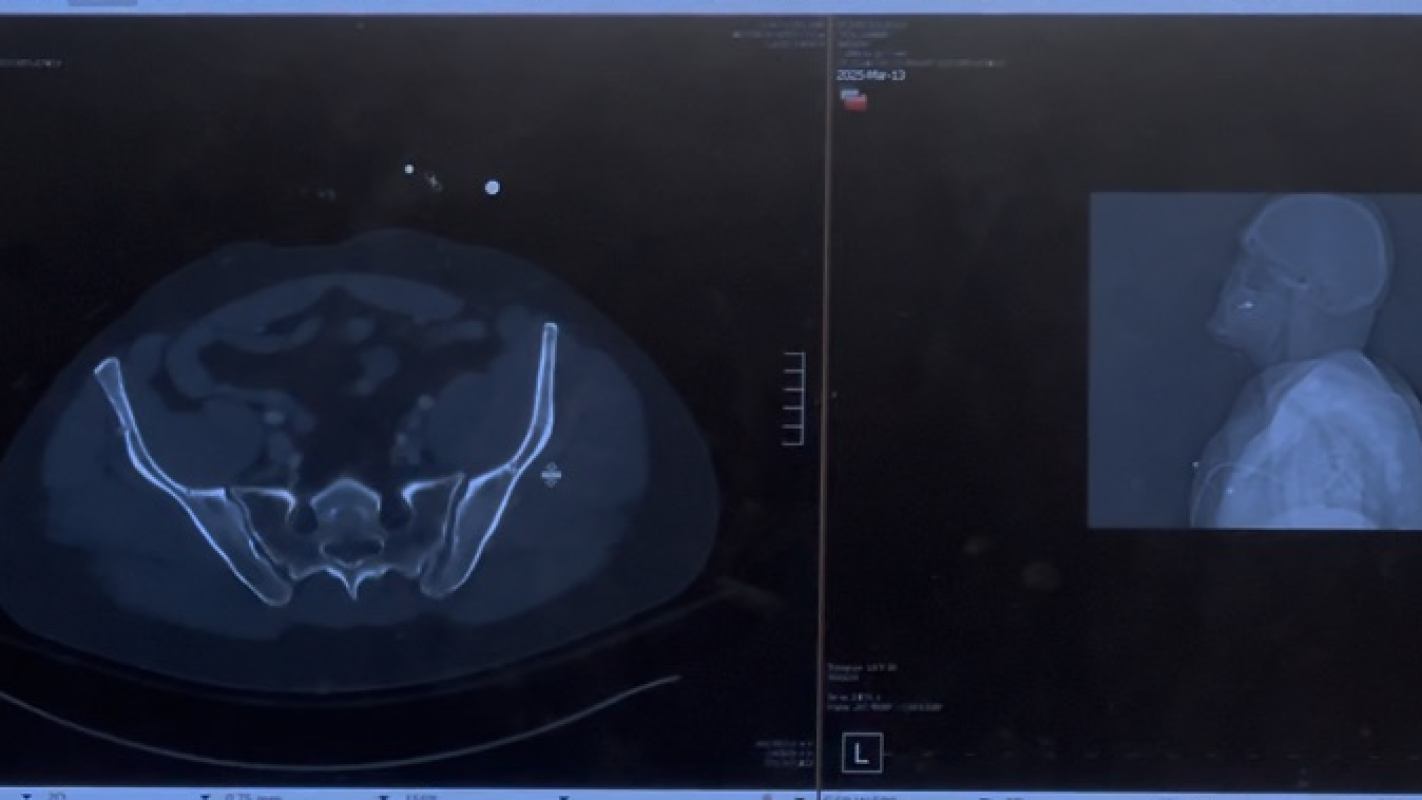

Fundraising to help get back on his feet to walk again from a shattered pelvis and extended stay in hospital with specialized surgery. All your support is greatly appreciated ; thanks to all family and friends and within allegheny health network for all efforts ongoing. Funds to help give back and to ease transition w more forward progress ; and humble thanks ahead.